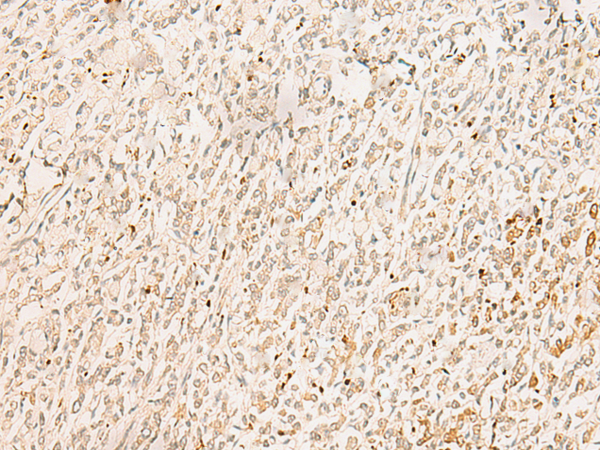

分类: 科研抗体货号: P02993别名: F5F8D; SDNSF; F5F8D2; LMAN1IP应用: IHC反应种属: Human, Mouse, Rat